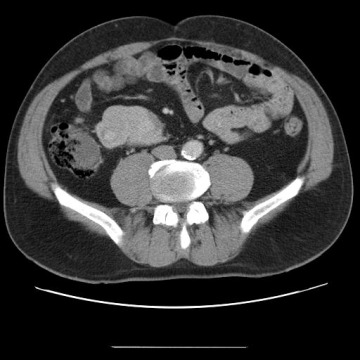

CT břicha 24.10.2006 (obr.1-7): játra nezvětšená, přiměřené denzity, s vícečetnými hypodenzními, lehce neostře ohraničenými ložisky, největší velikosti 20x16 mm je v 4A segmentu, drobnější (10 mm) je v 8. segmentu a další nejméně tři ještě drobnější (do 5 mm) jsou v 6. a 4. segmentu. Pankreas, slezina, nadledviny bpn. Vpravo v ledvině korová cysta velikosti 20 mm. Vpravo v meso-hypogastriu jsou v průběhu terminálního ilea dvě patolog. expanze (či jedna dvoulaločnatá), které se zřetelně sytí po kontr. látce. Jedna je v oblasti Bauhinské chlopně, má velikost 36x25x25 mm, větší mediálnější je velikosti 73x44x43 mm. Expanze jsou vcelku dobře ohraničené, v okolí bez přesvědčivé desmoplastické reakce. V oblasti kořene mesenteria vpravo jen drobné (do 7 mm) ojedinělé lymf. uzliny, mírně větší ojedinělá uzlina je paraaortálně (15x8 mm). Bez volné tekutiny v dutině břišní. Baze plic bpn. Na skeletu bez ložiskových změn. Závěr: dvě patologické expanze v oblasti terminálního ilea (karcinoid dle histol. vyš.), bez známek infiltrace okolí. V.s. vícečetná drobná metastatická ložiska v játrech.

Obr.č.1: CT vyšetření břicha

/ Obr.č.1: CT vyšetření břicha /